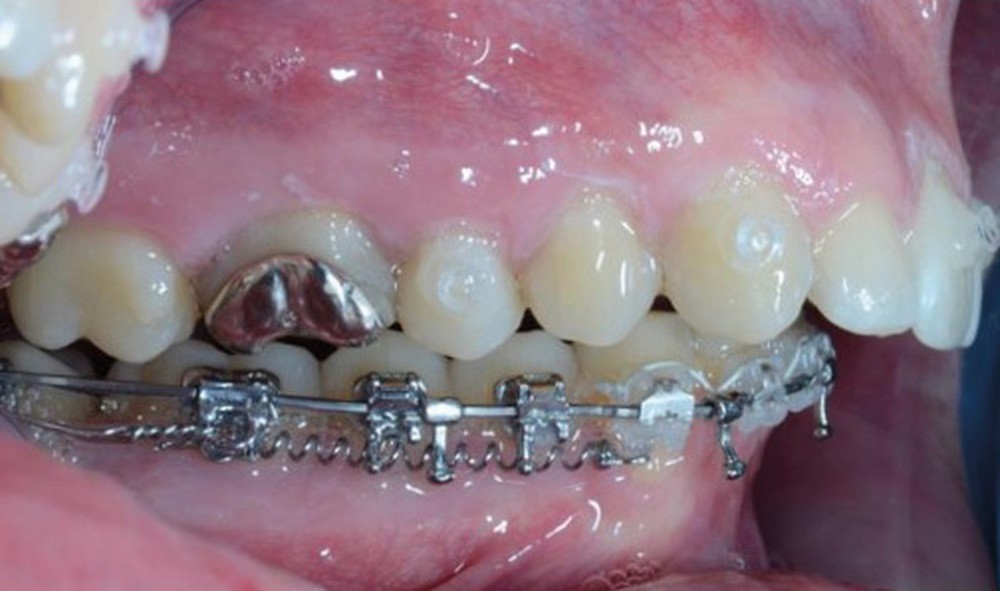

C’est à ces questions que nous permettront de répondre les deux premiers conférenciers, parodontologistes : le Dr Béatrice Straub nous présentera le renfort parodontal minéralisé, technique qu’elle a développée et pratique depuis de nombreuses années, pour éviter les préjudices des mouvements orthodontiques à risque, notamment lors des décompensations préchirurgicales (fig. 1a-d) ; le Pr Anton Sculean abordera le thème des greffes, avec leurs indications, les différentes techniques à privilégier et illustrera ses propos par de nombreux cas cliniques aux résultats esthétiques impressionnants.

À côté de la coopération moindre qu’ils exigent, les ancrages squelettiques présentent également l’avantage de répondre à des indications très variées : correction des sourires gingivaux (Dr Skander Ellouze, fig. 3a-c), distalisation ou mésialisation molaire, supports pour les masques faciaux, mini transpalatin sur vis après expansion, ressorts de rétraction pour mettre en place les canines incluses sans léser les racines des dents adjacentes [3] (Dr Stéphane Renger, fig. 4) ou appareils d’expansion maxillaire (Dr Hans Winsauer, Dr Guido Sampersmans, fig. 5a-c)…